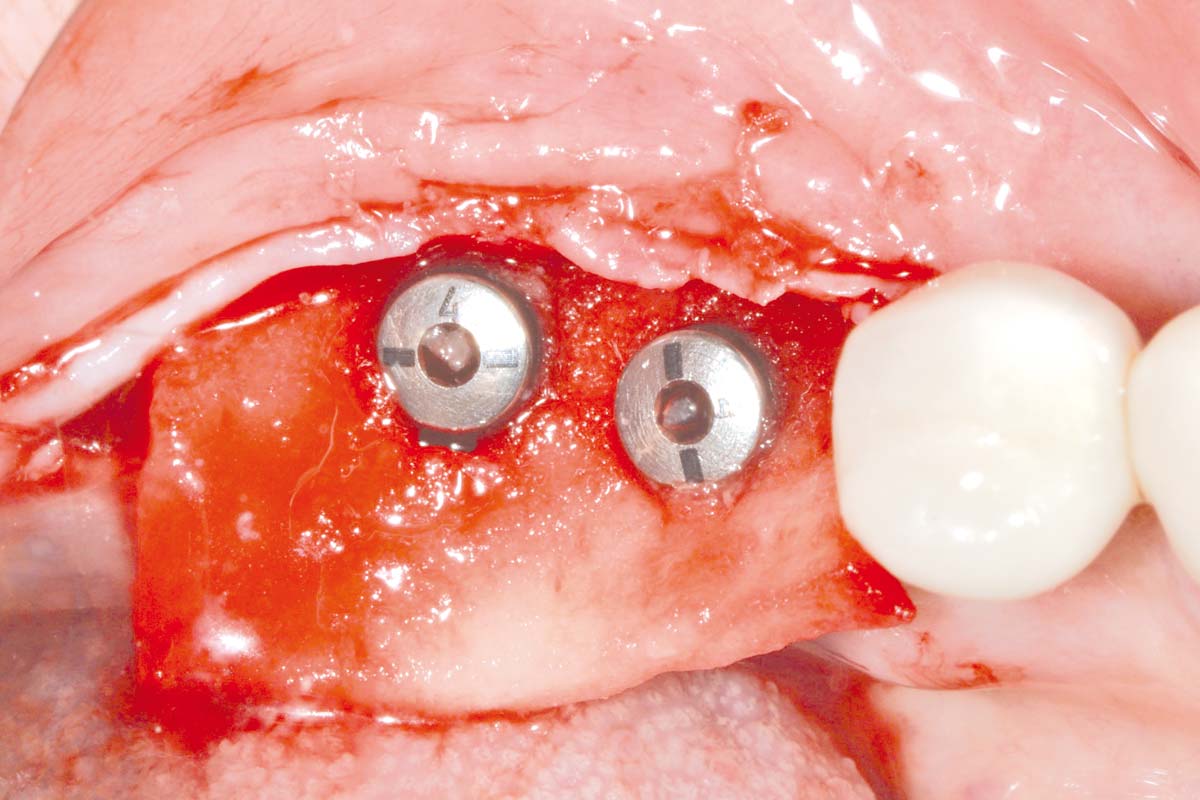

4/16 - Placement of short implantsPeri-implant soft tissue thickening with mucoderm® - Dr. F. Rojas-Vizcaya

5/16 - Placed implantsPeri-implant soft tissue thickening with mucoderm® - Dr. F. Rojas-Vizcaya